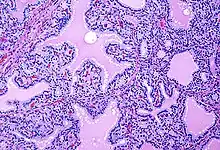

Histopathology of a case of Grave's disease. It shows marked hyperplasia of thyroid follicular cells, generally more so than toxic multinodular goitre, forming papillae into the thyroid follicles, and with scalloping of the peripheral colloid.